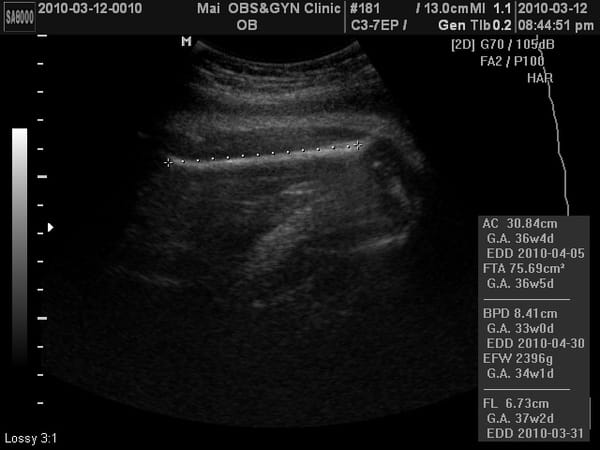

《小老虎》37W第九次產檢報告

小老虎第九次產檢,驗尿ok,血壓………,母親體重65.9KG,兩周共增重1.2KG。 乙型鏈球菌檢驗正常。 小老虎上次產檢2500公克,這次2600多公克,這兩周吃的東西都長在媽媽身上。 血壓:112/54 心跳:………. 這次又看得到4D照了,相當有肉,臉頰有肉、鼻子有肉、嘴巴也很有肉、連胸部也擠出一團肉~~~ (但是這周 […]…